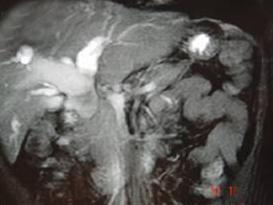

问题 女,35岁,右上腹痛1月,黄疸进行性加重,AFP阴性,消瘦乏力,影像检查如图,最可能的诊断为()

选项 A.肝转移癌 B.胆管癌 C.局灶性脂肪肝 D.原发性肝癌 E.肝血管瘤

答案 B